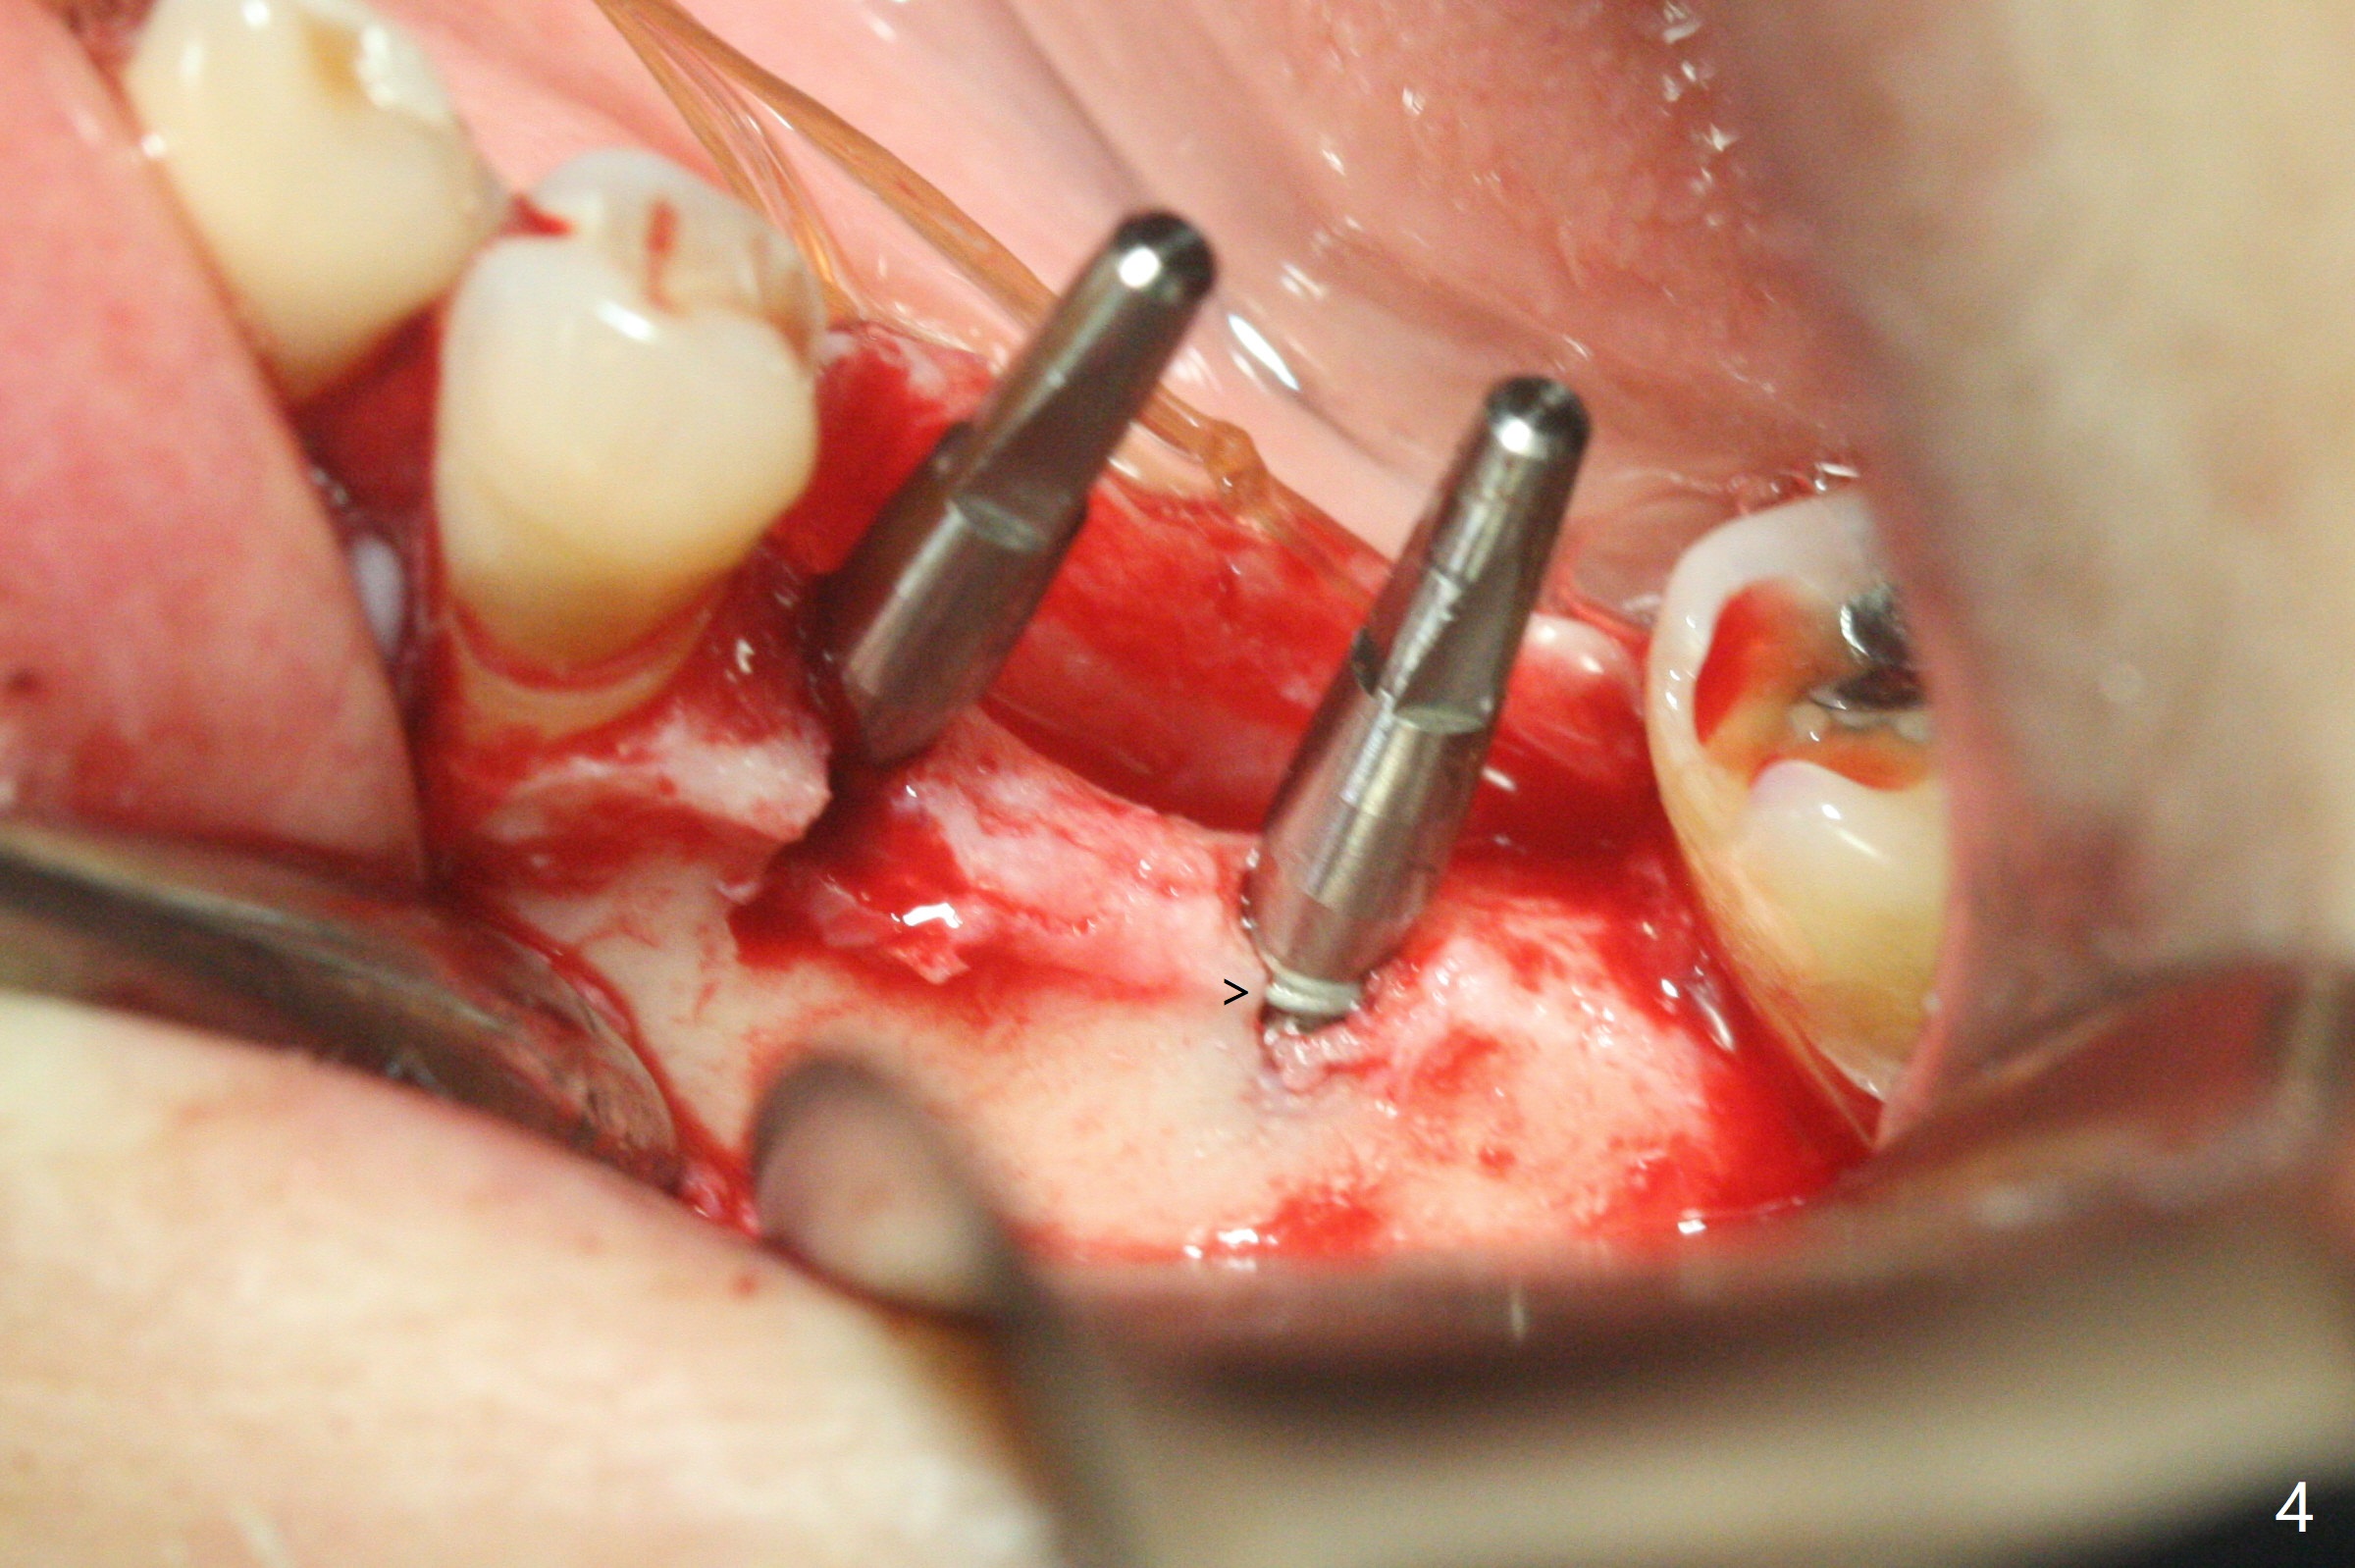

左下5,6切开,使用导板钻洞,都偏向颊侧(图一),好像牙槽嵴太狭窄,不适合做劈开术,然后改为自由手,使用Lindermann(侧方)钻头将钻洞往舌侧迁移,完成一段式植体初步钻洞(图二)以及植体植入(图三:2.5毫米(直径),根据近远中距离,植体不显得太窄)。尽管下齿槽神经阻断麻醉(开始浸润麻醉),病人疼痛明显,不敢下沉远中植体太多(图四:>),放置粘性骨块(图五,六:*)和PRF膜。缝合后,调整基台以及对合牙高度(图六: <),最后放置牙周敷料。由于植骨,术后15天植体周围形成致密的牙龈带(图七:*(gingival band))。术后一个月安置临时连体牙冠,没有任何咬合接触,主要目的防止7近中倾斜。术后三个半月临时牙冠被吞入,右侧托牙也不见了,局部牙龈健康,塞入2-0 gingival retraction cord(增加5基台长度(今后牙冠固位),图八 (>:植体螺丝刀终止地方)),取模。永久性牙冠边缘不重要,由实验室决定。清除残余粘固剂也不是很困难(图九)。